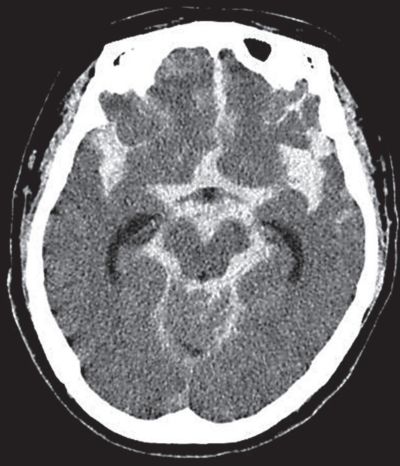

その後、直ちに胸骨圧迫およびバッグバルブマスク換気を開始し、静脈路確保を行った。アドレナリンを静脈投与した後に、自己心拍が再開し、心拍数 90/分、整。血圧 126/72 mmHg となった。自発呼吸は認めなかったため気管挿管を行い集中治療室へ入院となった。意識レベルは JCSⅢ-300 から JCSⅢ-100 となった。SpO2 は 98 %(吸入酸素濃度 60 %)であった。自発呼吸は回復しなかった。入院後に撮影した頭部単純 CTを別に示す。